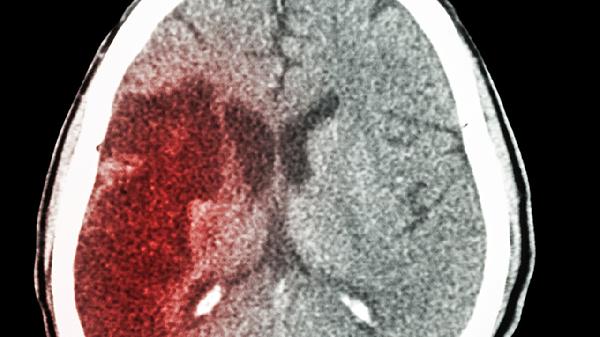

不同于普通头痛,这种疼痛像被闪电劈中,伴随恶心呕吐。可能是蛛网膜下腔出血的征兆,需要立即就医。